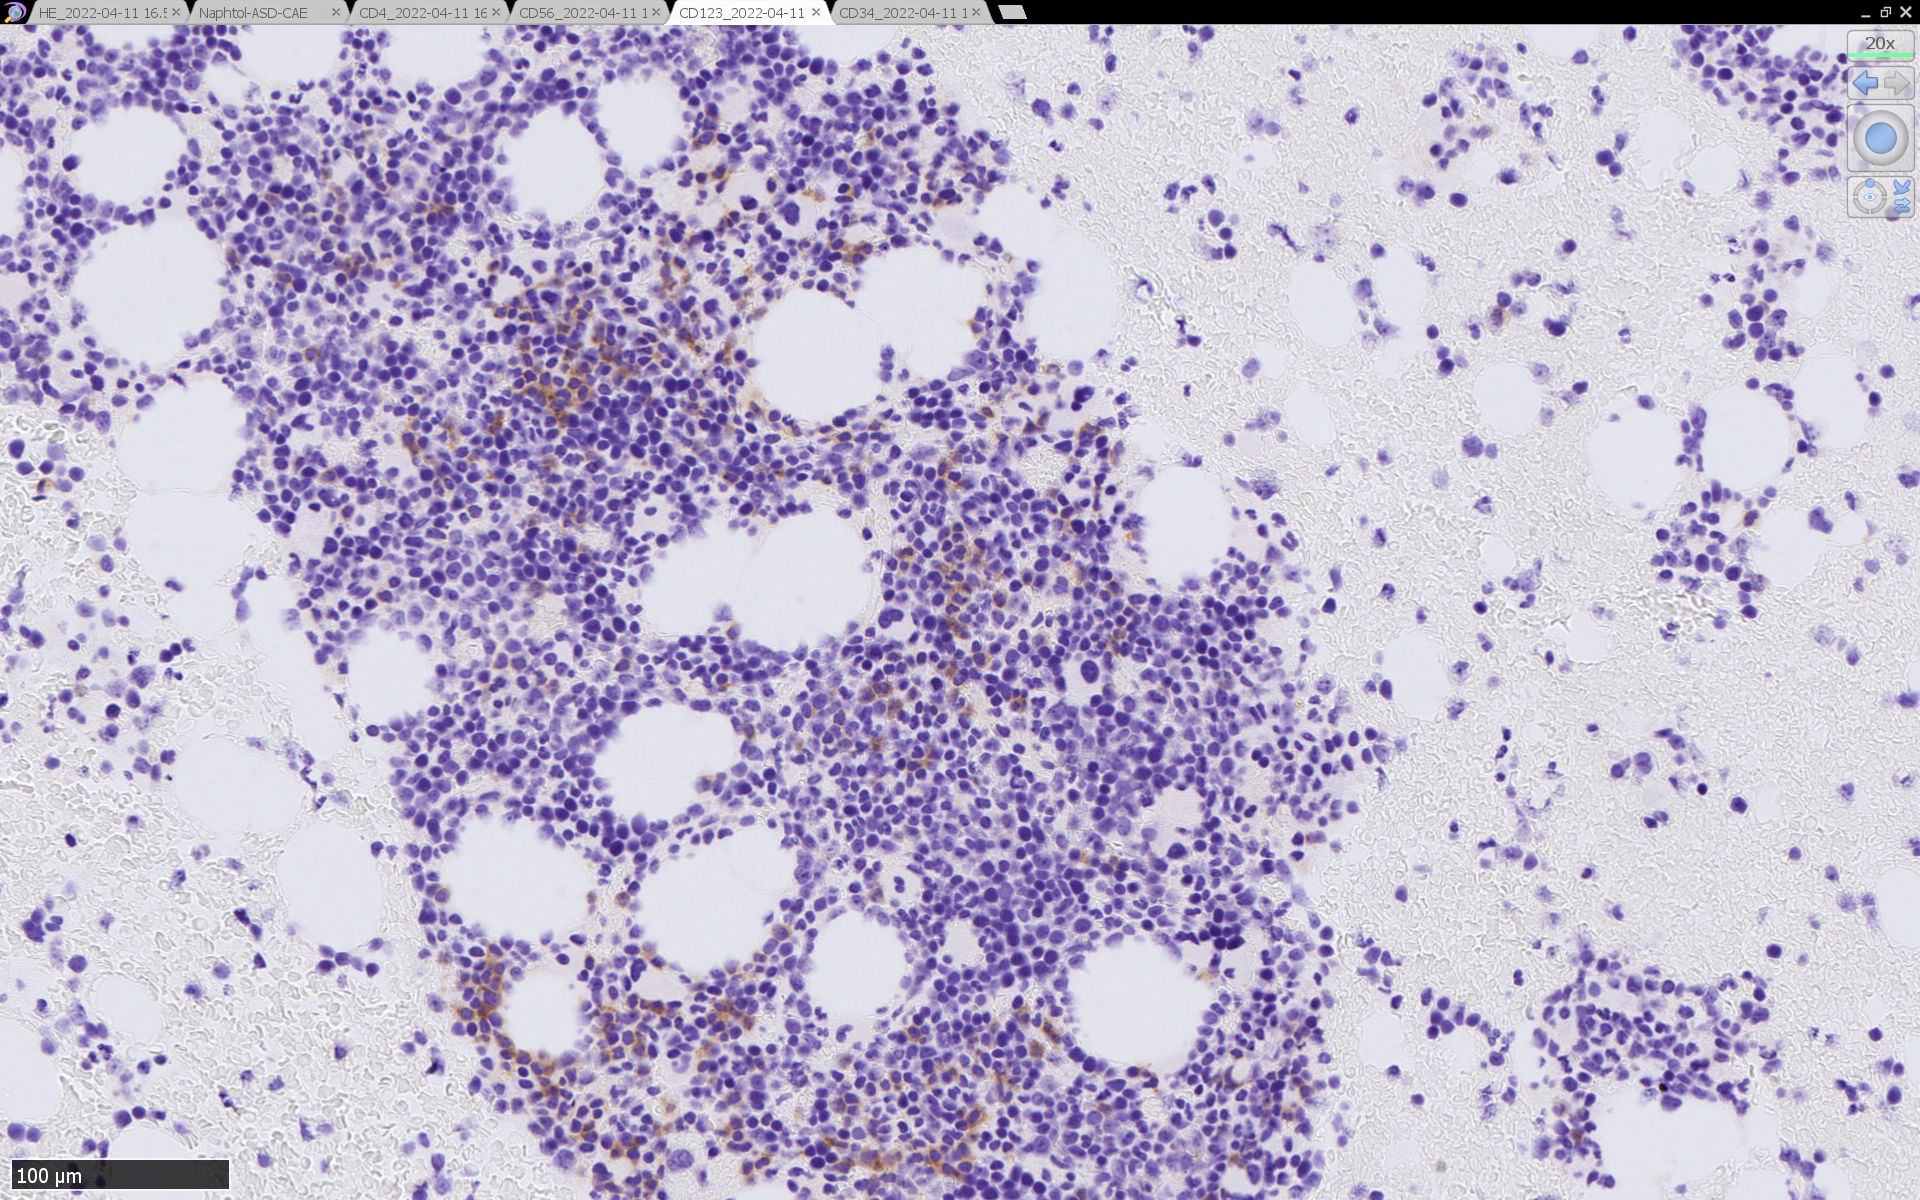

免疫染色

HEでは腫瘍細胞の同定が難しい. 本症例は ASD-Giemsa染色を見ても, 腫瘍胞巣はよくわからなかった. 皮膚が先に診断がつき, 次いでBone marrowだったため, 免疫染色にすすめたが, Bone marrowが先だと診断に困ったかもしれない.

CD4は染まりすぎの感がある(濃く染まる細胞はCD4+ T-cellかもしれない). CD56, CD123が陽性で可能性が高くなり, BPDCNの診断にはCD34は陰性であることが必要

TCF4、CD123、TCL1をconsultationにより染色していただき, 陽性を確認した. CD34-, lysozyme-, CD123(おいてある病院は少ないかも)をしらべて, BPDCN研究会あてconsultationをする流れでしょうか.